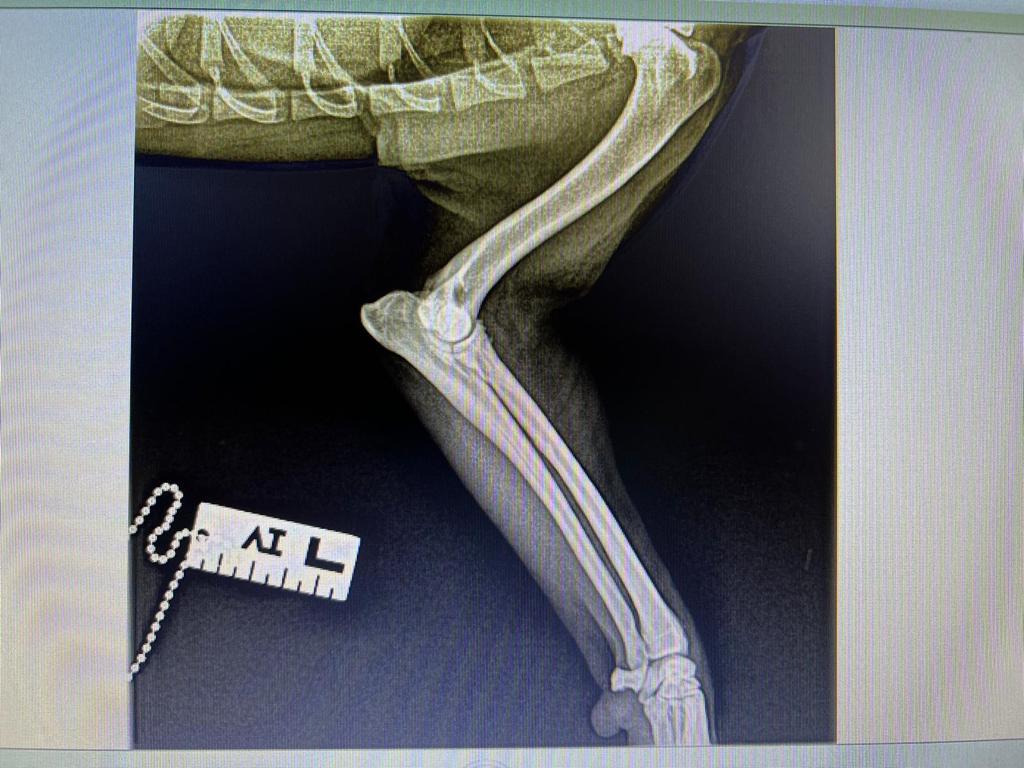

Rüde, Mischling, 3 Jahre, Vermittelt, stammt aus Italien, TierNr. 5213

Bullo

Mischling

3 Jahre

Rüde